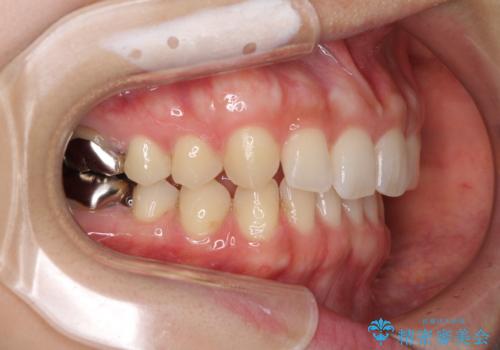

- 前歯の隙間と奥歯の目立つ銀歯を気にして来院された患者様です。

インビザラインにより下顎前歯の隙間を閉じるとともに、奥歯の咬み合わせを改善させることとしました。

矯正治療後には、銀歯のクラウンをセラミッククラウンへ替える補綴治療を行うこととしました。

左右奥歯の咬み合わせを変更させる必要があったため、治療期間は長くなることが予想されました。

1日22時間以上の装着時間をしっかりと守ってくださったので、順調に治療を進めることができました。